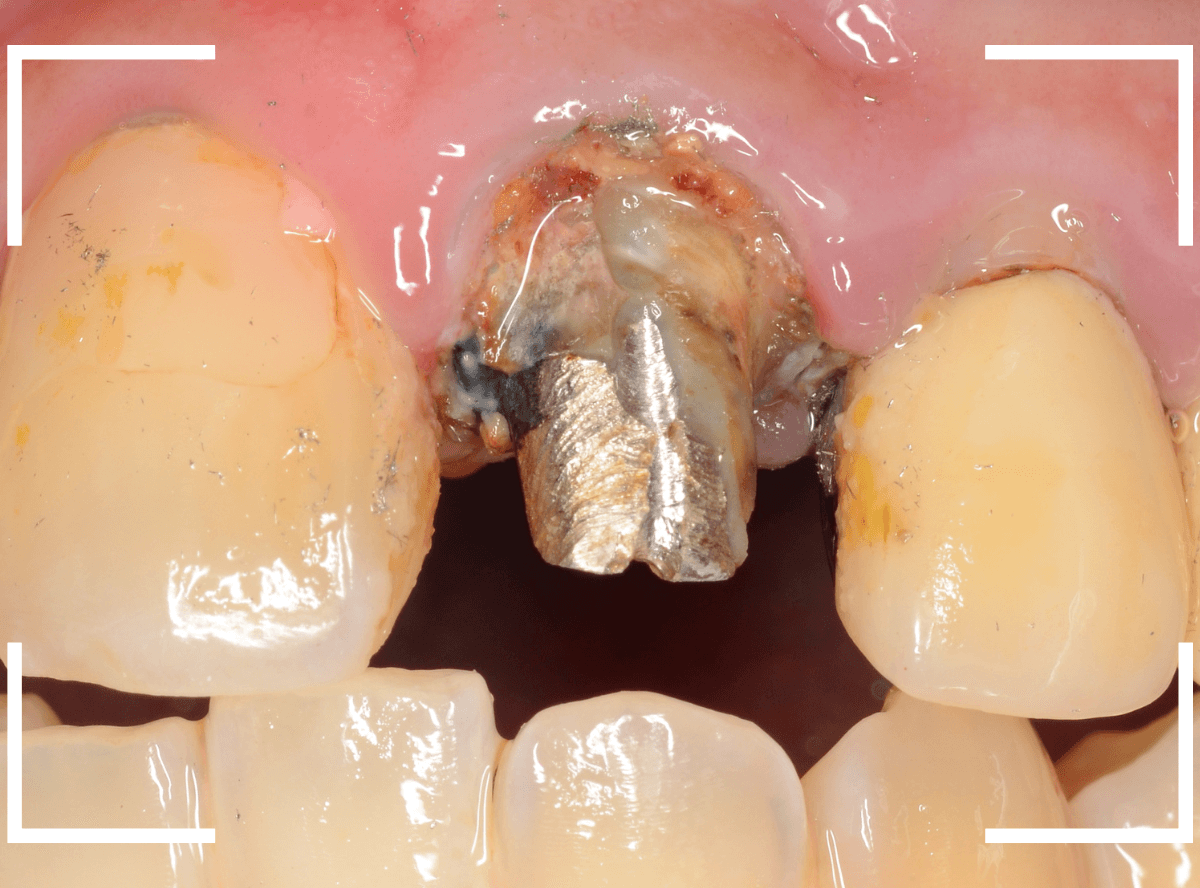

患者さんに状況を説明して、さし歯を外して確認します。

さし歯の中は、虫歯も進行しており、想像以上にひどい状況になっているのがわかります。

この状況では、いくら歯ブラシをしてもすぐにすき間に汚れがたまってしまうでしょう。

土台(メタル・コア)も外しつつ、虫歯を除去します。

赤く染色されている部分は虫歯です。

土台の中も虫歯になっていました。

早い段階で治療が出来てよかったです。

そして、後ろの歯との境の〇部には汚れや歯石が多くつまっています。

虫歯と共に、歯の周りの縁下歯石除去も行いました。

歯の周りがきれいになっているのがわかると思います。